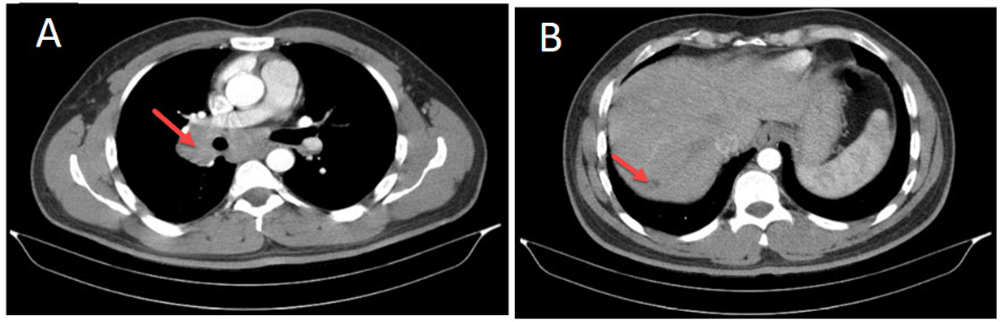

A 39-year-old man, taxi driver, known to have hypothyroidism (being treated with levothyroxine) presented to the emergency ward with dyspnea and coughing after exposure to detergents in a closed environment. The patient was smoker (3 pack/year). The only in clinical examinations except for wheezing in the right side of chest. The patient's chest radiography identified a mass. For further investigation, a spiral computerized tomography (CT) scan was performed. Lymph nodes were enlarged on the right side of the trachea, measuring about 23 mm with a mass of 70 × 77 mm, in the vicinity of the right lung hilum. A hypodense nodule in the posterior part of the liver, suspected to be malignant, was also reported (Figure 1). The lesions were suspected to be metastatic tumors, therefore, a biopsy of the mass was performed via bronchoscopy. The biopsy results were reported as chronic inflammation and mucosal hyperplasia without malignancy, which did not conform to the CT report. The CT has repeated again, and confirmed the previous CT report. A CT guided mass biopsy was performed for pathological evaluation. The result showed chronic granulomatous inflammation, the two most likely causes being tuberculosis (TB) and sarcoidosis. Sputum smear, culture, and PCR were performed to test for TB, and angiotensin-converting enzyme (ACE) levels were measured for sarcoidosis. The results ruled out TB and showed high levels of ACE (ACE = 88 (normal 8-53)). Two months after the first visit, sarcoidosis was diagnosed and treatment started with prednisolone. Ophthalmology test for eye evaluation, echocardiography for cardiac evaluation and EMG/NCV (Electromyogram test and nerve conduction study) for evaluation of the nervous system were also performed to determine if there was any extra-pulmonary sarcoidosis, however, no lesions were found. After treatment by corticosteroid the symptoms of the patient subsided. Now the patient is on follow-up. Figure 2 show the CT scan of patient after treatment.

CT scan in-patient with sarcoidosis-(A) Pulmonary lymphadenopathy and (B) granulomatous lesion in Liver involvement.